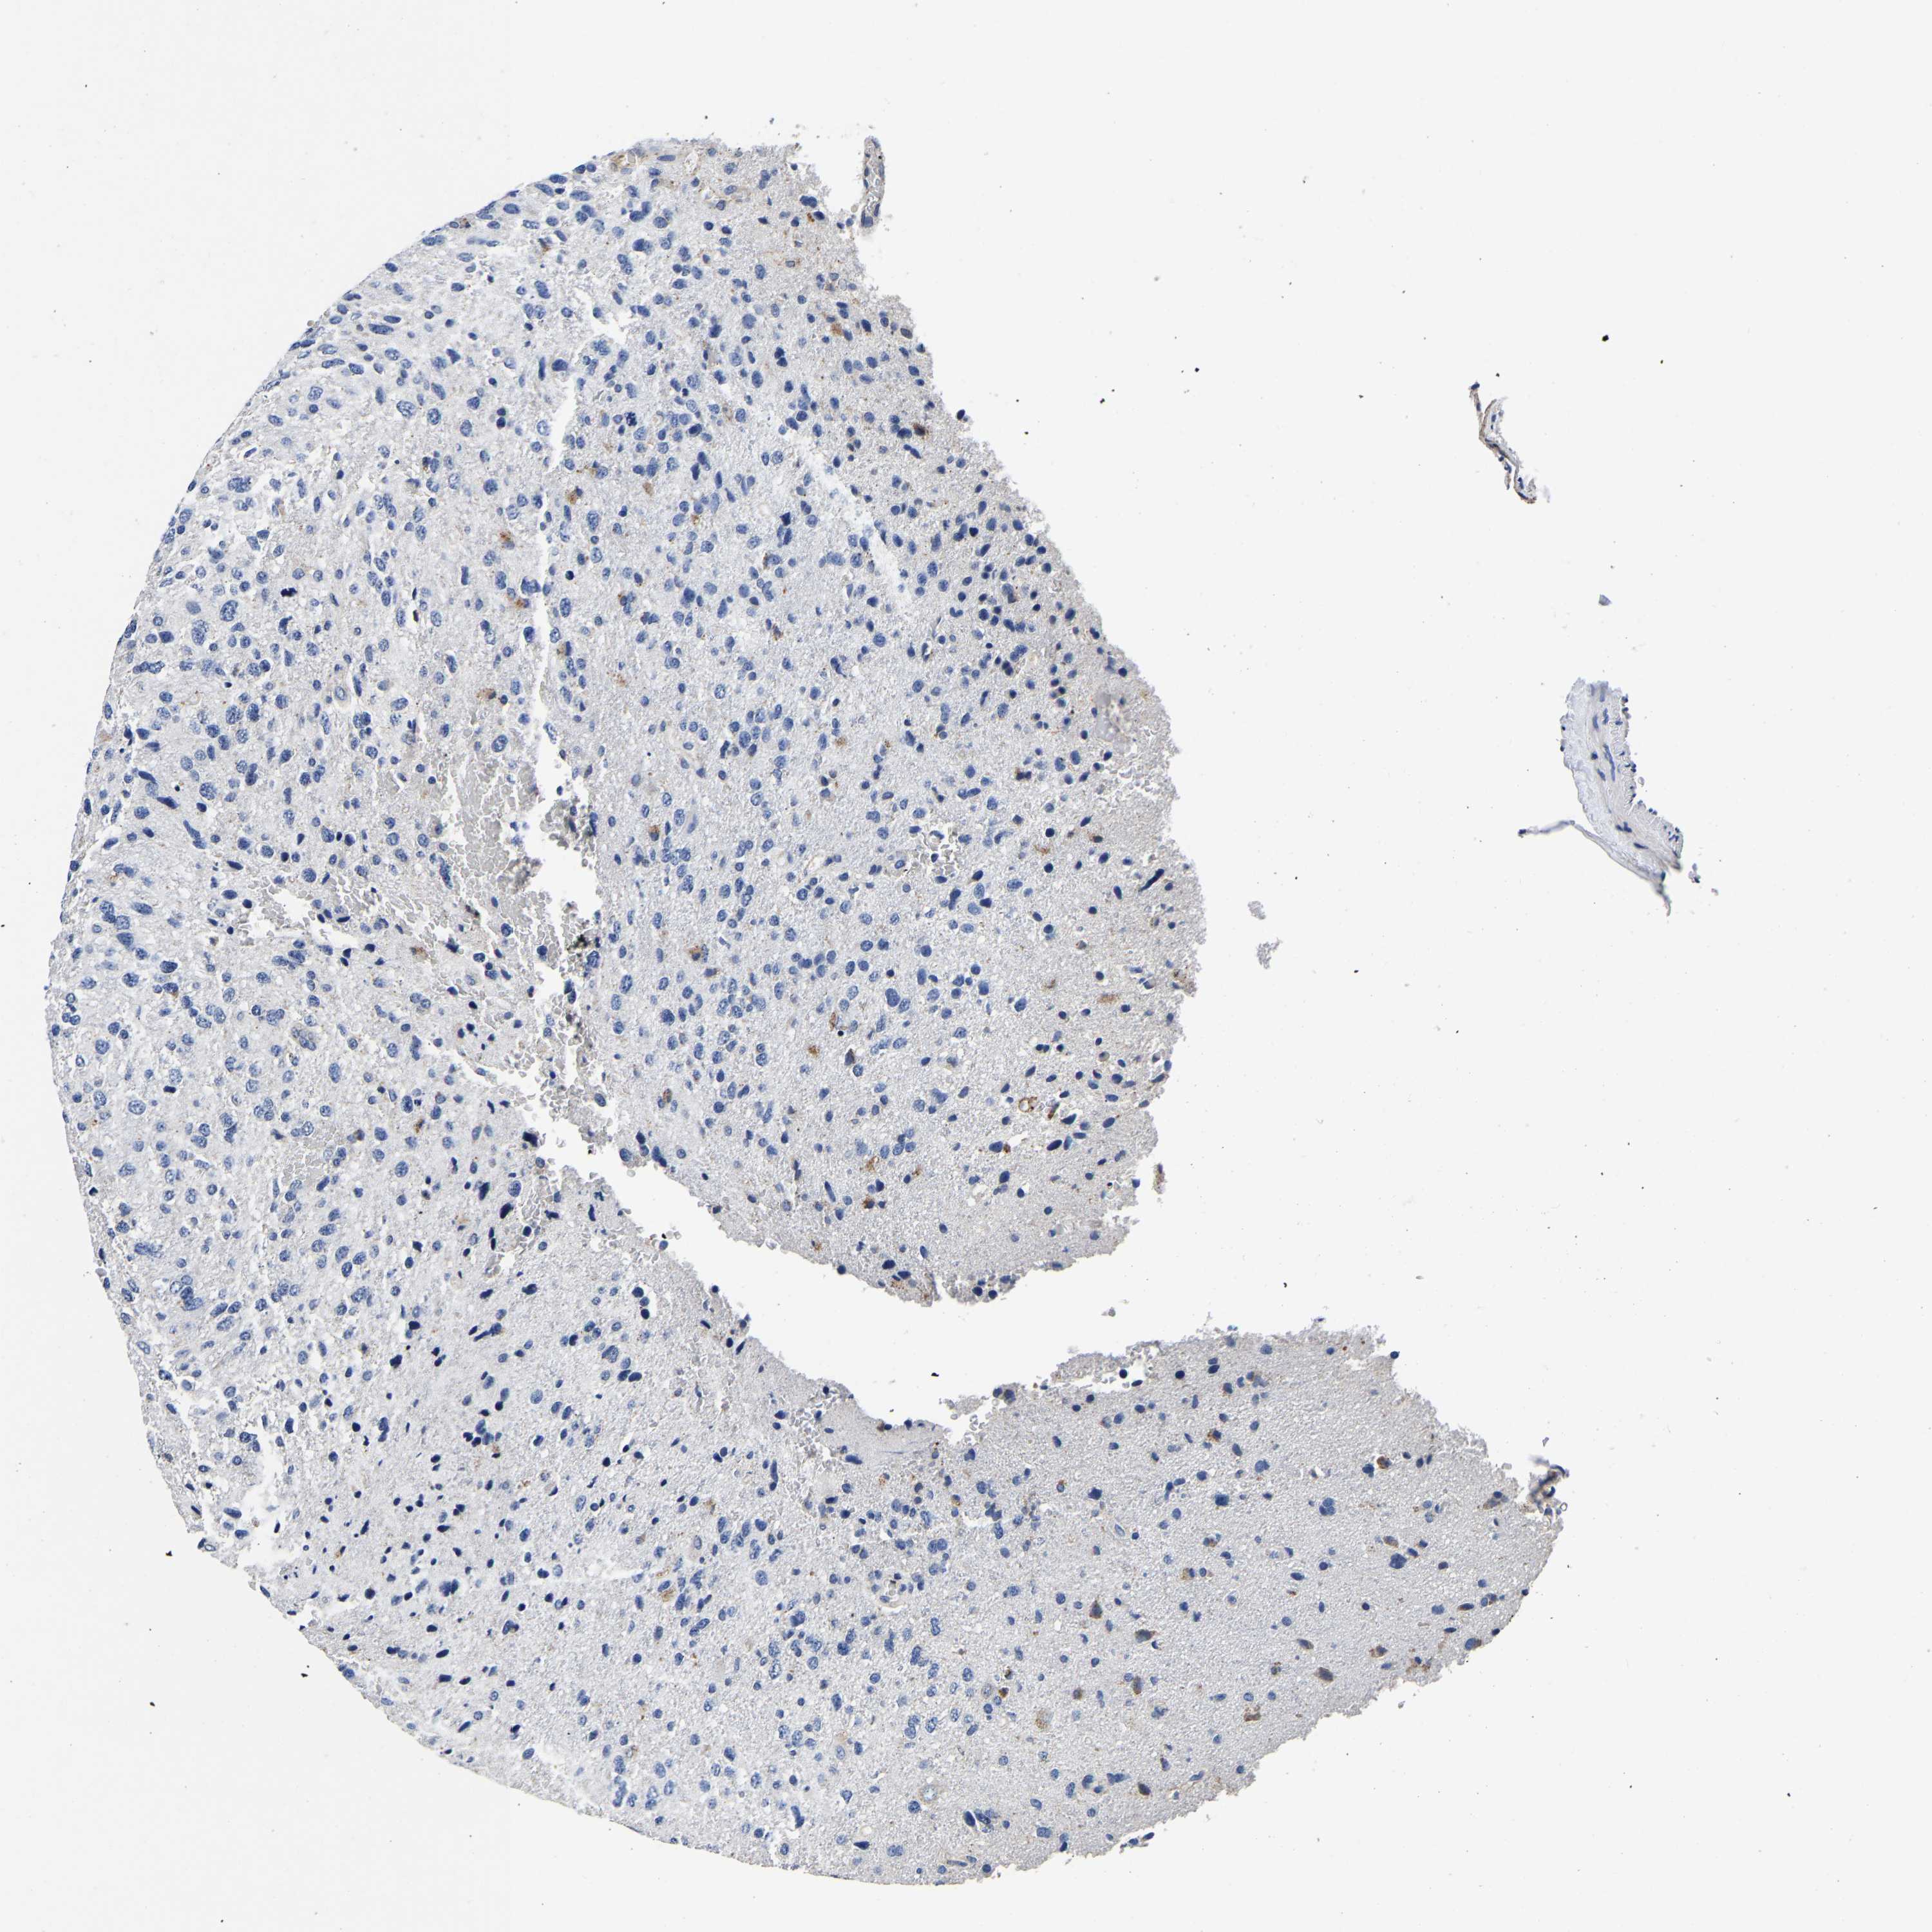

GLIOMA - Protein expressioni

A mouse-over function shows sample information and annotation data. Click on an image to view it in a full screen mode. Samples can be filtered based on level of antibody staining by selecting one or several of the following categories: high, medium, low and not detected. The assay and annotation is described here.

Note that samples used for immunohistochemistry by the Human Protein Atlas do not correspond to samples in the TCGA dataset.

Antibody stainingi

Antibody staining in the annotated cell types in the current human tissue is reported as not detected, low, medium, or high, based on conventional immunohistochemistry profiling in selected tissues. This score is based on the combination of the staining intensity and fraction of stained cells.

Each image is clickable and will lead to virtual microscopy that enables deeper exploration of all samples and also displays staining intensity scores, fraction scores and subcellular localization as well as patient and tissue information for each sample.

Antibody HPA008763

Antibody HPA028747

Antibody CAB019394

Staining

High

Medium

Low

Not detected

Intensity

Strong

Moderate

Weak

Negative

Quantity

>75%

75%-25%

<25%

None

Location

Nuclear

Cytoplasmic/membranous

Cytoplasmic/membranous,nuclear

Glioma, malignant, High grade

Glioma, malignant, Low grade